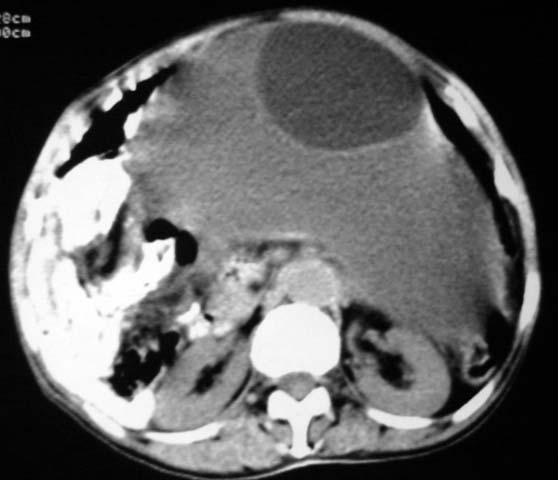

女,75岁,腹部胀大半年余,无其他症状。

考虑来源与卵巢的巨大囊腺瘤或囊肿。

考虑卵巢巨大囊腺瘤可能性大.

卵巢巨大囊腺瘤可能。

考虑来源卵巢巨大黏液性囊腺瘤。